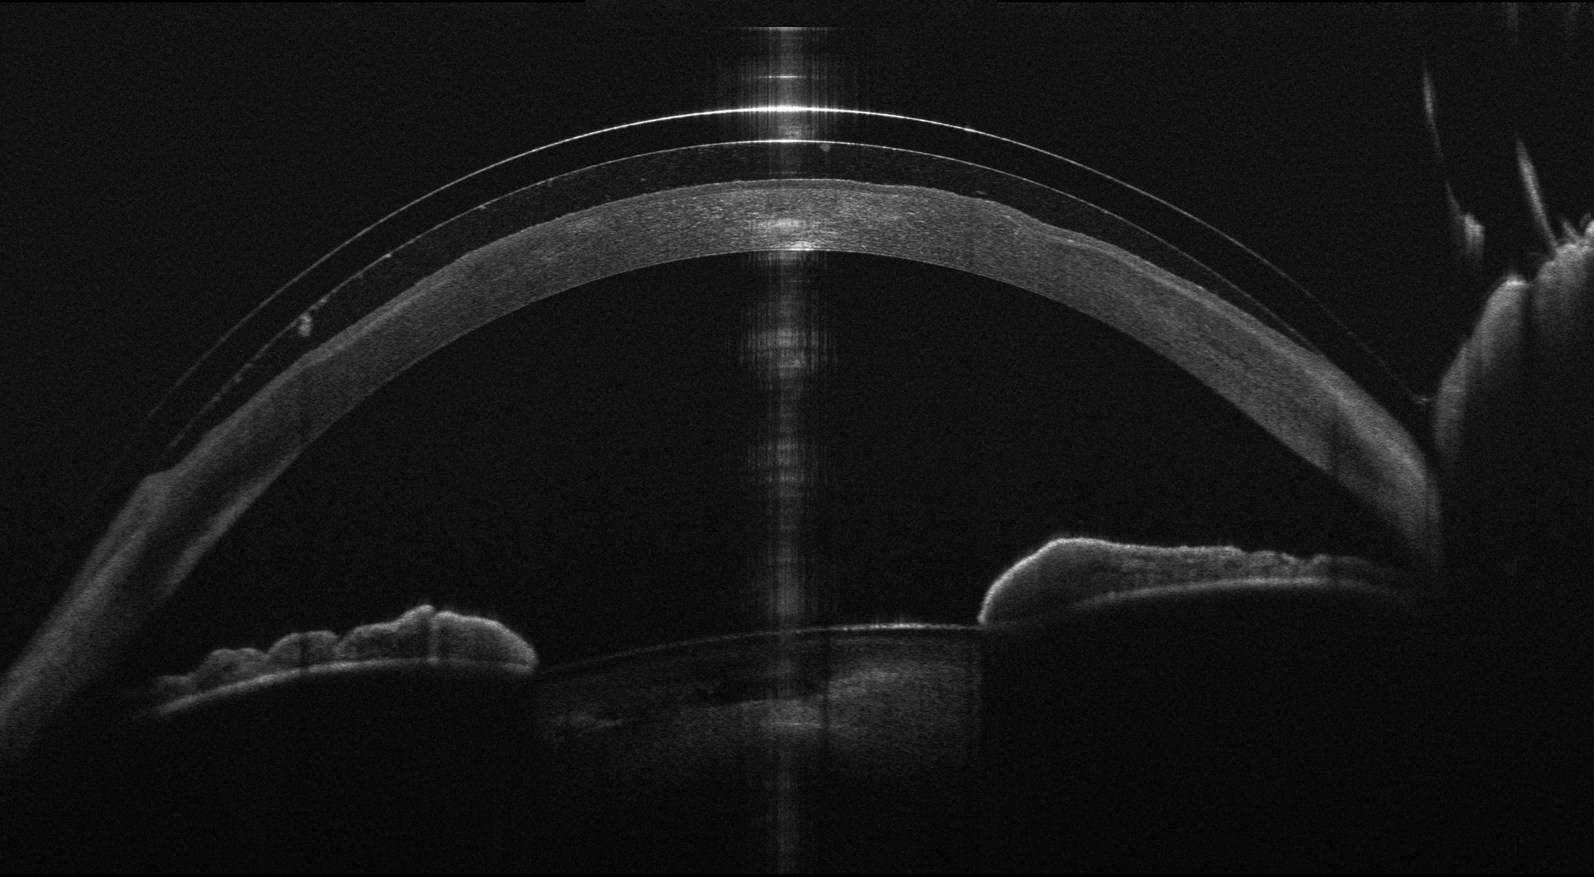

Le lenti a contatto sclerali sono la massima espressione della contattologia specialistica per la correzione dei difetti visivi causati da irregolarità della superfice corneale. Sono realizzate in materiale rigido ultra gas permeabile e disegnate per coprire completamente l'intera volta corneale e la sua periferia.

L'appoggio è circolare ed extracorneale sulla congiuntiva sclerale. In questo modo la lente rimane sollevata dalla cornea, non creando interazione meccanica, permettendo di tutelare la superfice corneale spesso molto delicata in chi necessita questo tipo di lenti. lo spazio che si crea tra la lente e la cornea viene colmato con soluzione salina non conservata che viene instillata nella lente al momento dell'inserimento, così la cornea rimane sempre adeguatamente bagnata, rendendo queste lenti molto utili anche per le persone con secchezza oculare.

Il grande diametro delle lenti sclerali permette di ottenere un completo ripristino funzionale della cornea unito a un comfort insuperabile, molto simile a quello delle lenti morbide.